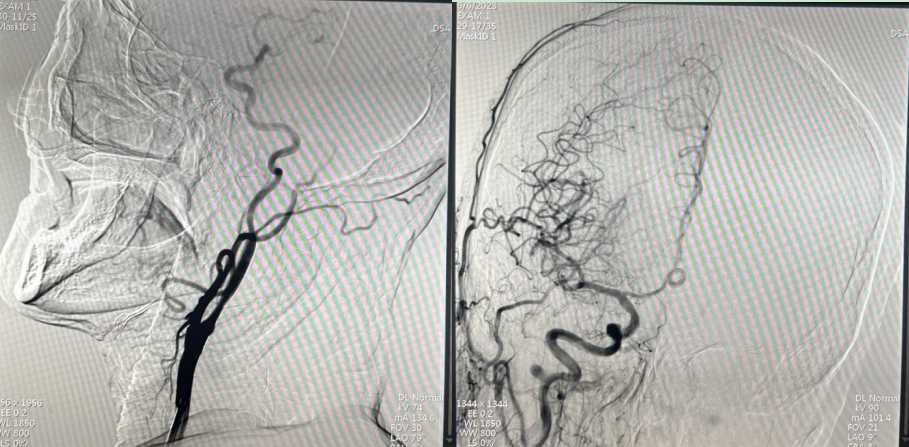

图二:颈内动脉球囊扩张+支架植入术后